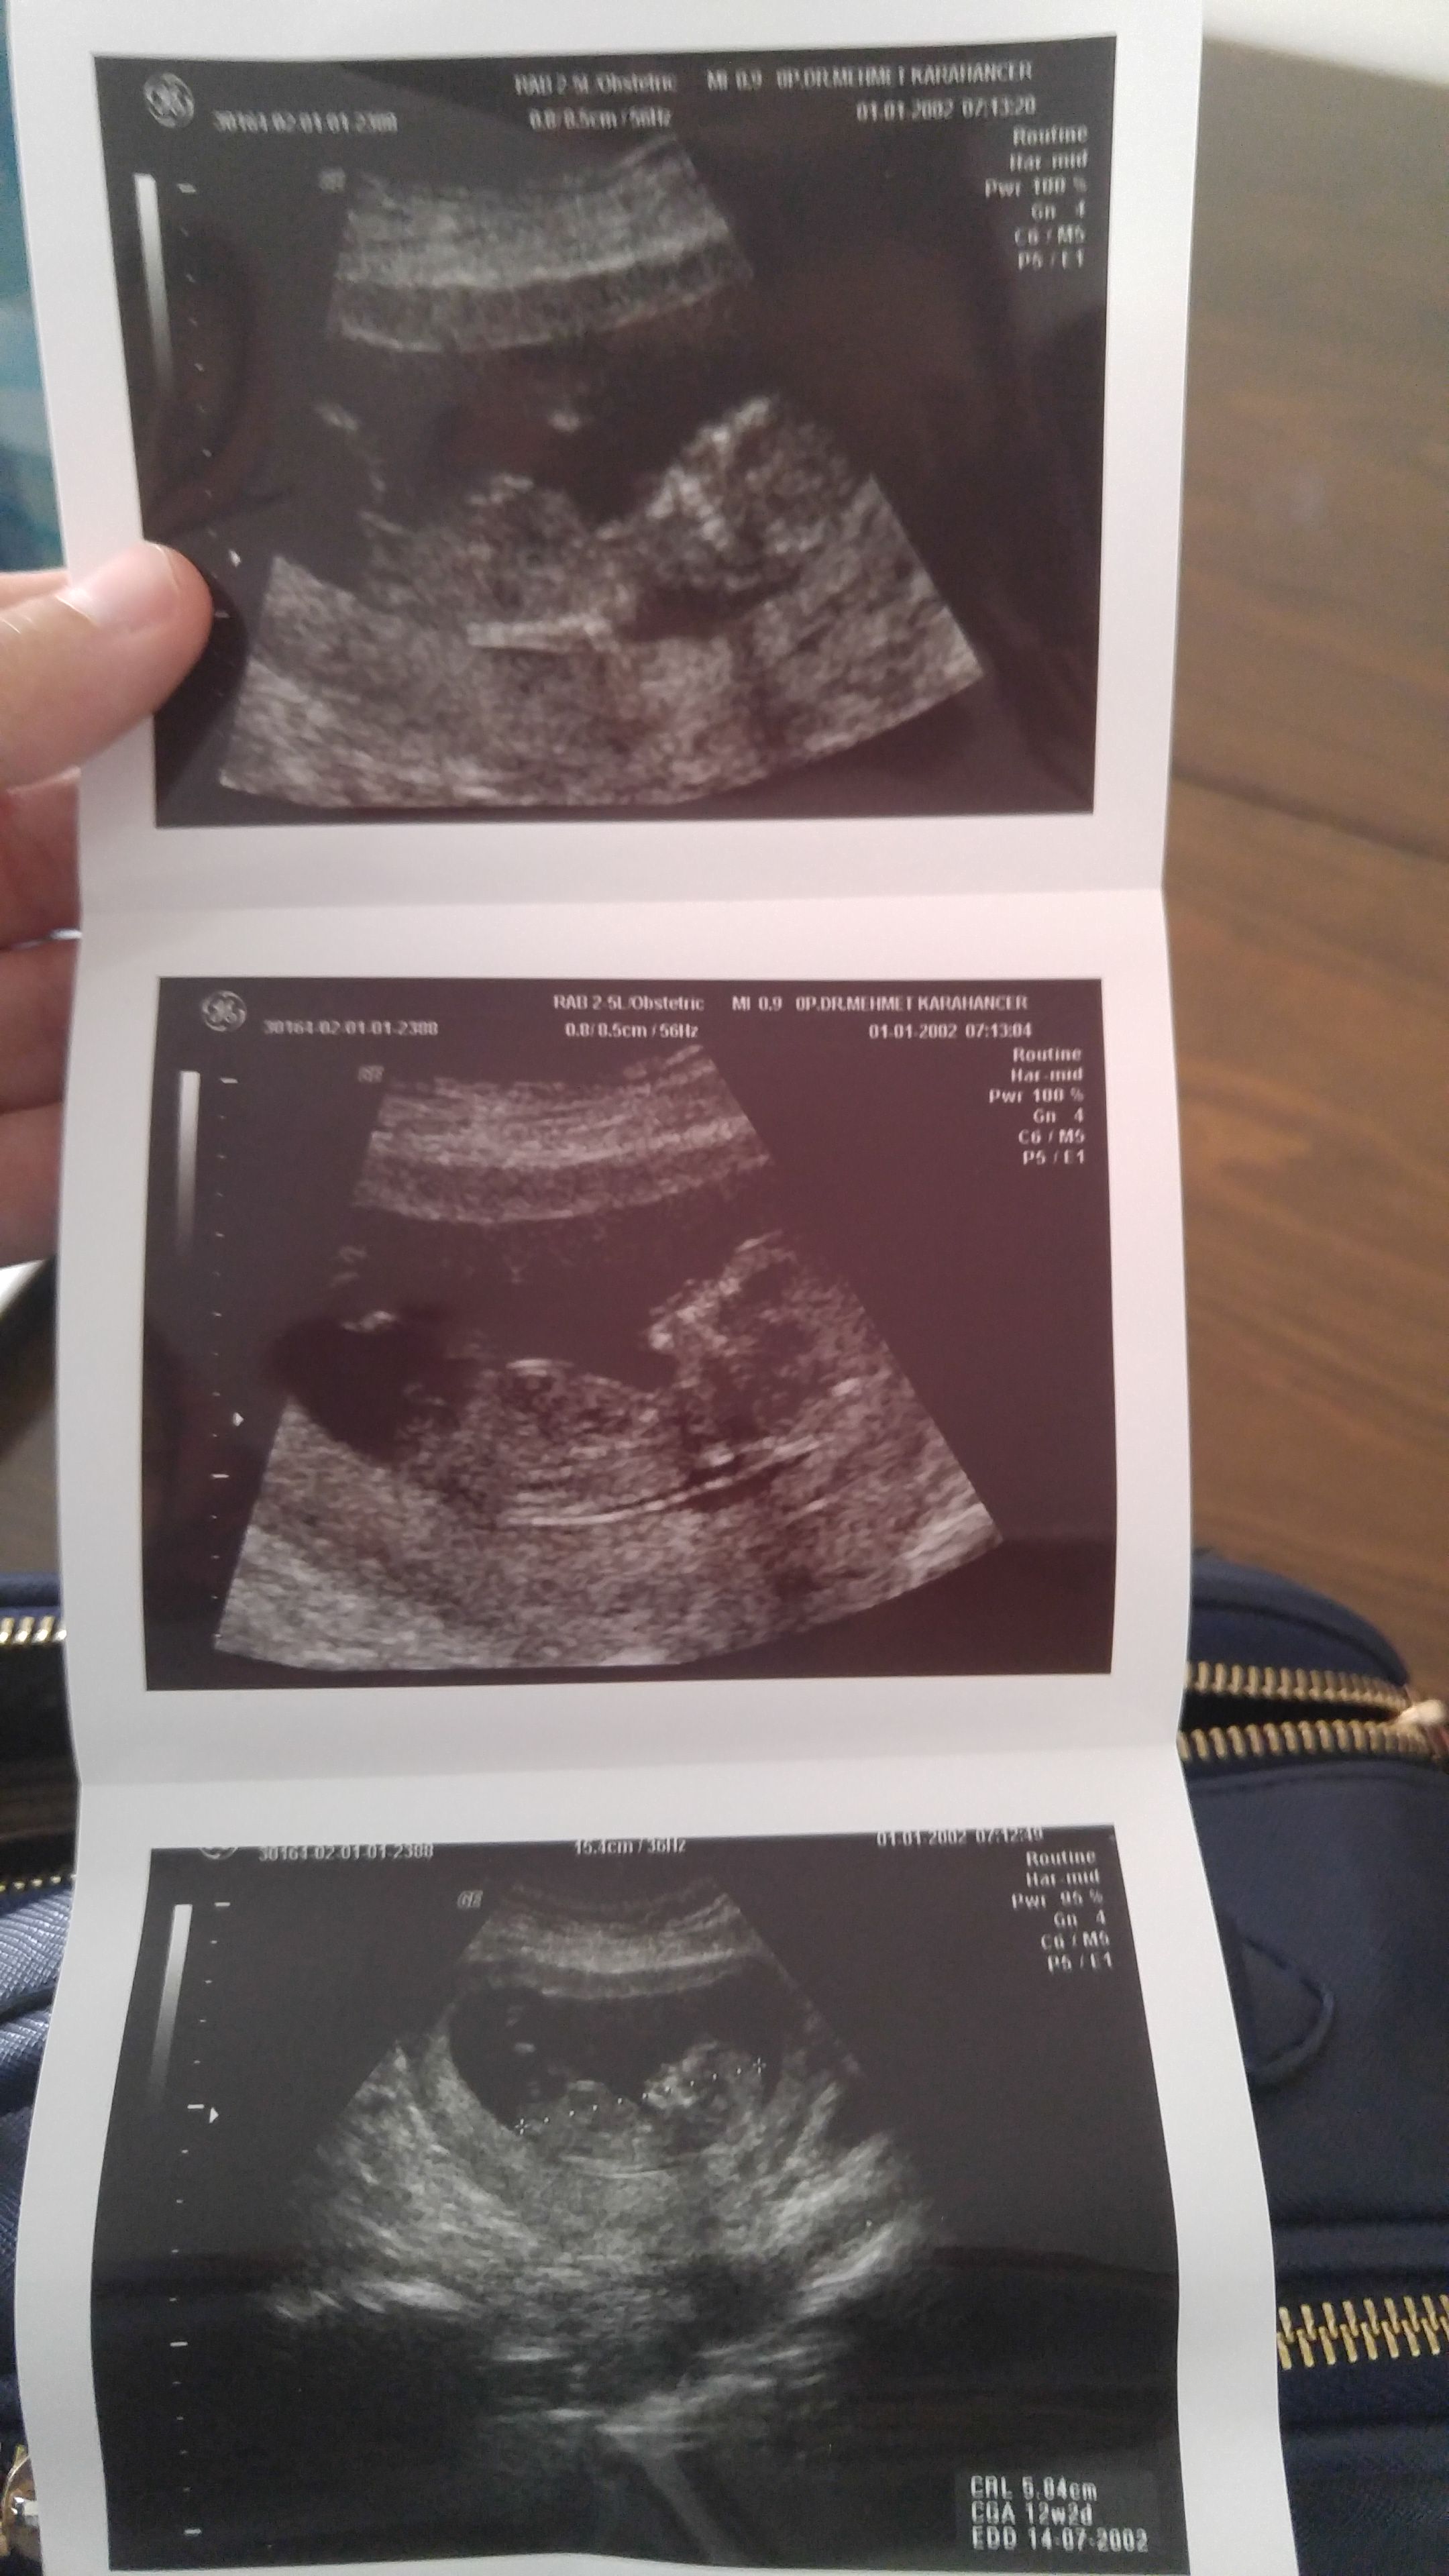

1 1234tmm Yeni Üye Üye 29 Nisan 2017 #264 Ekli dosyayı görüntüle 76263 Ekli dosyayı görüntüle 76264 Ekli dosyayı görüntüle 76264